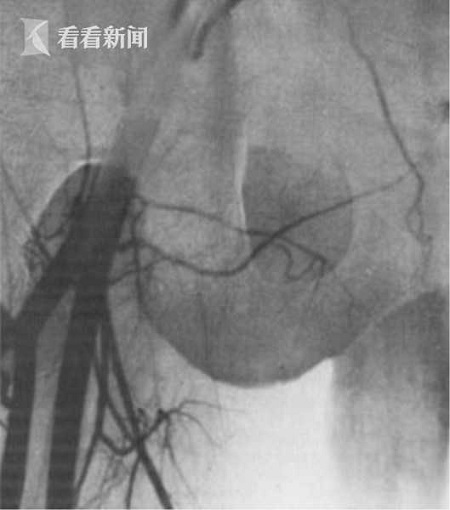

手术期间,医疗团队必须同时将双胞胎兄弟的阴囊切开,进行睾丸移植,并在极为有限的时间内,将阴囊内的两根动脉、两根宽不到两毫米的静脉成功缝合。

另据专业人士介绍称,一旦把睾丸从捐赠者体内取出后,必须在之后的2到4个小时内,重新“接上线”。睾丸在无血液注入的情况下,最多只能存活6个小时。